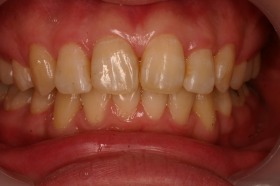

歯の矯正治療 症例ビフォー&アフター

ご覧の症例は出っ歯を矯正治療でキレイにしたケースです。

よく出っ歯は日本人に多いようなイメージがありますが

、世界的に見ても受け口と比較して出っ歯は多いようです。

このような場合では歯を抜いて矯正するか

、抜かずに矯正するか分かれるケースです。

ご覧の矯正歯科治療の場合は、抜いて矯正歯科

治療していますが東京世田谷矯正歯科センターでは

非抜歯矯正歯科治療をベースにしています。

どうしても抜かないとキレイにならない場合のみ

抜歯して矯正歯科治療しています。